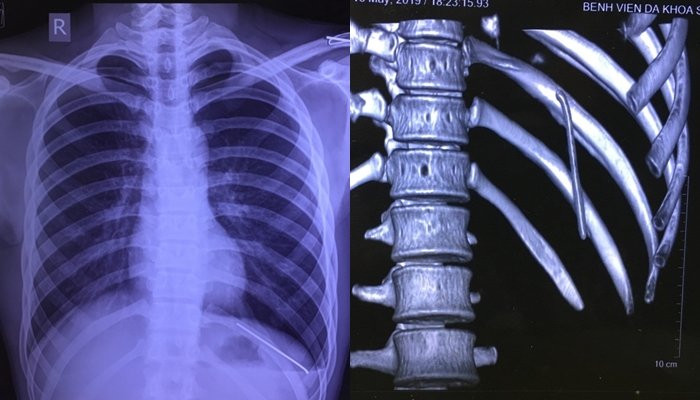

Hình ảnh chiếc đinh trong khoang phổi nam bệnh nhân. (Ảnh: BVCC)

Sau khi hội chẩn và thăm khám thêm, bác sĩ phát hiện anh H. có dị vật kim khí trong khoang màng phổi trái, kèm theo tràn khí màng phổi. Để điều trị, các bác sĩ tư vấn anh nên về quê, nhập Bệnh viện Đa khoa tỉnh Phú Thọ phẫu thuật.

Nguyên nhân là do chiếc đinh di chuyển từ vị trí xương đòn trái theo thời gian nó rơi tự do vào trong khoang màng phổi trái.